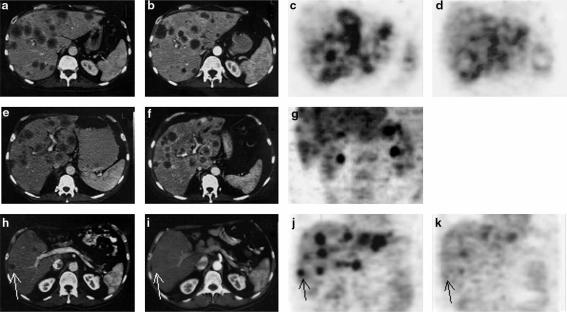

Regression of liver metastases was confirmed in computed tomography 2 months after vector administration. The size of the index lesion decreased by 38% (from 31 mm×24 mm to 22 mm×21 mm). Likewise, a major improvement was demonstrated by positron emission tomography. The therapy was continued only with gemcitabine due to the closure of the trial; after 4 months computed tomography documented further regression of the index lesion to −80% of initial size (13×12 mm), but 6 months later the patient experienced progression of disease. Data are depicted in Figure 3.

Computed tomography and positron emission tomography scan examinations before and two months after administration of rAd/p53. In patient 1 (a–d), stable disease was documented after 2.5×1012 on days 2 and 3 and 23 and 24. Necrotic enhancement of the edge of the metastases (b). A slight reduction in 18F-Fluorodeoxyglucose activity suggests reduced metabolic activity of metastases (d). In patient 2 (e–g), progression was revealed in CT examination, therefore, no PET scan was obtained after two months. In patient 3 (h–k), regression of liver metastasis (arrows) was confirmed in computed tomography (h,i) and a major improvement was demonstrated in positron emission tomography (j,k) after administration of the adenoviral vector.